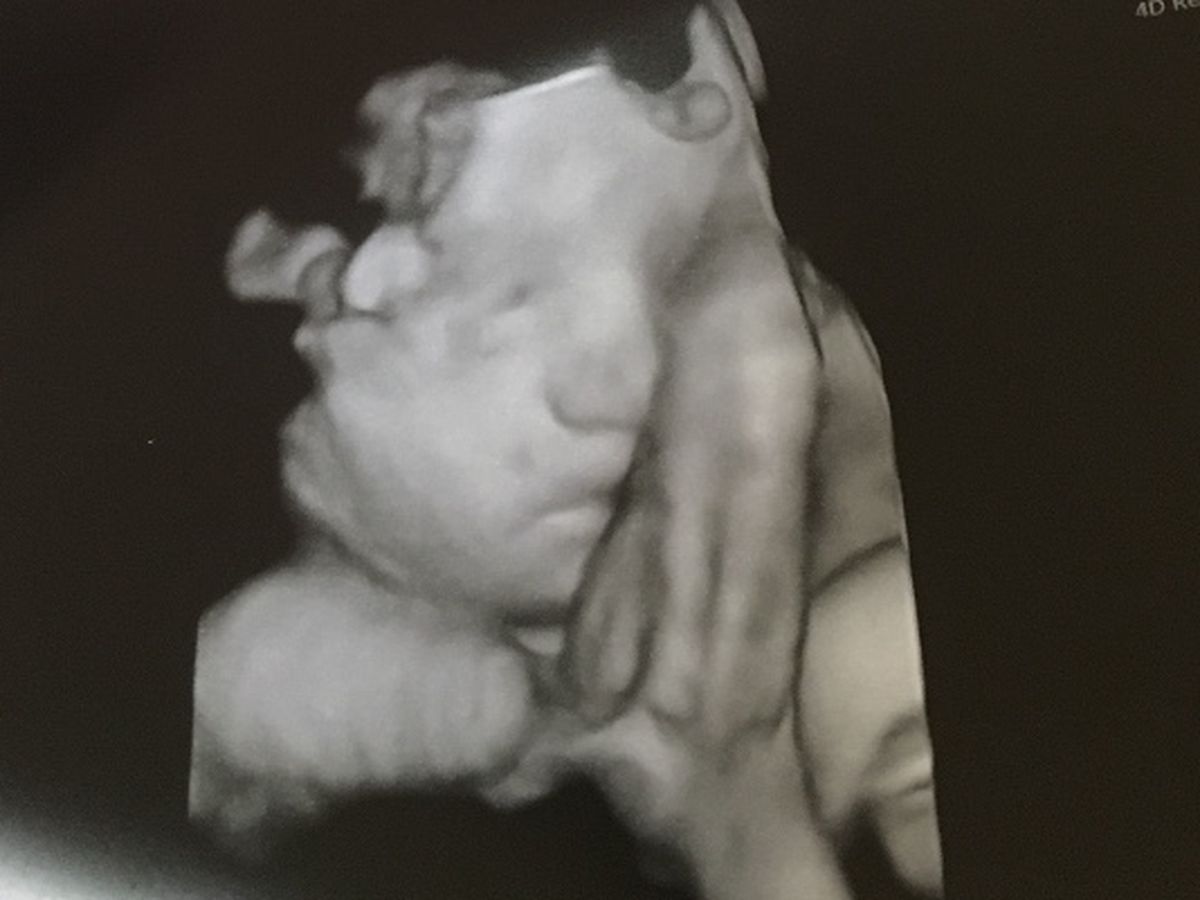

Perhaps one of the hardest things to do is to reach out for help, but when one stands at the fork in the crossroad and must choose which path to take, there is a clarity as never before, when the hour comes that you know from the depths of your heart, the precise place you must be. This is the place that Emily and Jeremiah now find themselves as they must contemplate the days, the weeks, and months ahead. What has become most clear for them is that they will do whatever it takes to travel this journey side by side with their precious son, Yadin, who will come into this world in just a few short weeks. At that exact moment, Yadin will be in the fight for his life. Literally, he will not have the ability to take one full breath for himself, when upon his birth he will have the first of what will be several life-saving surgeries. I come to petition on behalf of these brave parents and their precious son, Yadin, for this is a journey they undoubtedly know they could not make if they were to contemplate traveling this path alone.